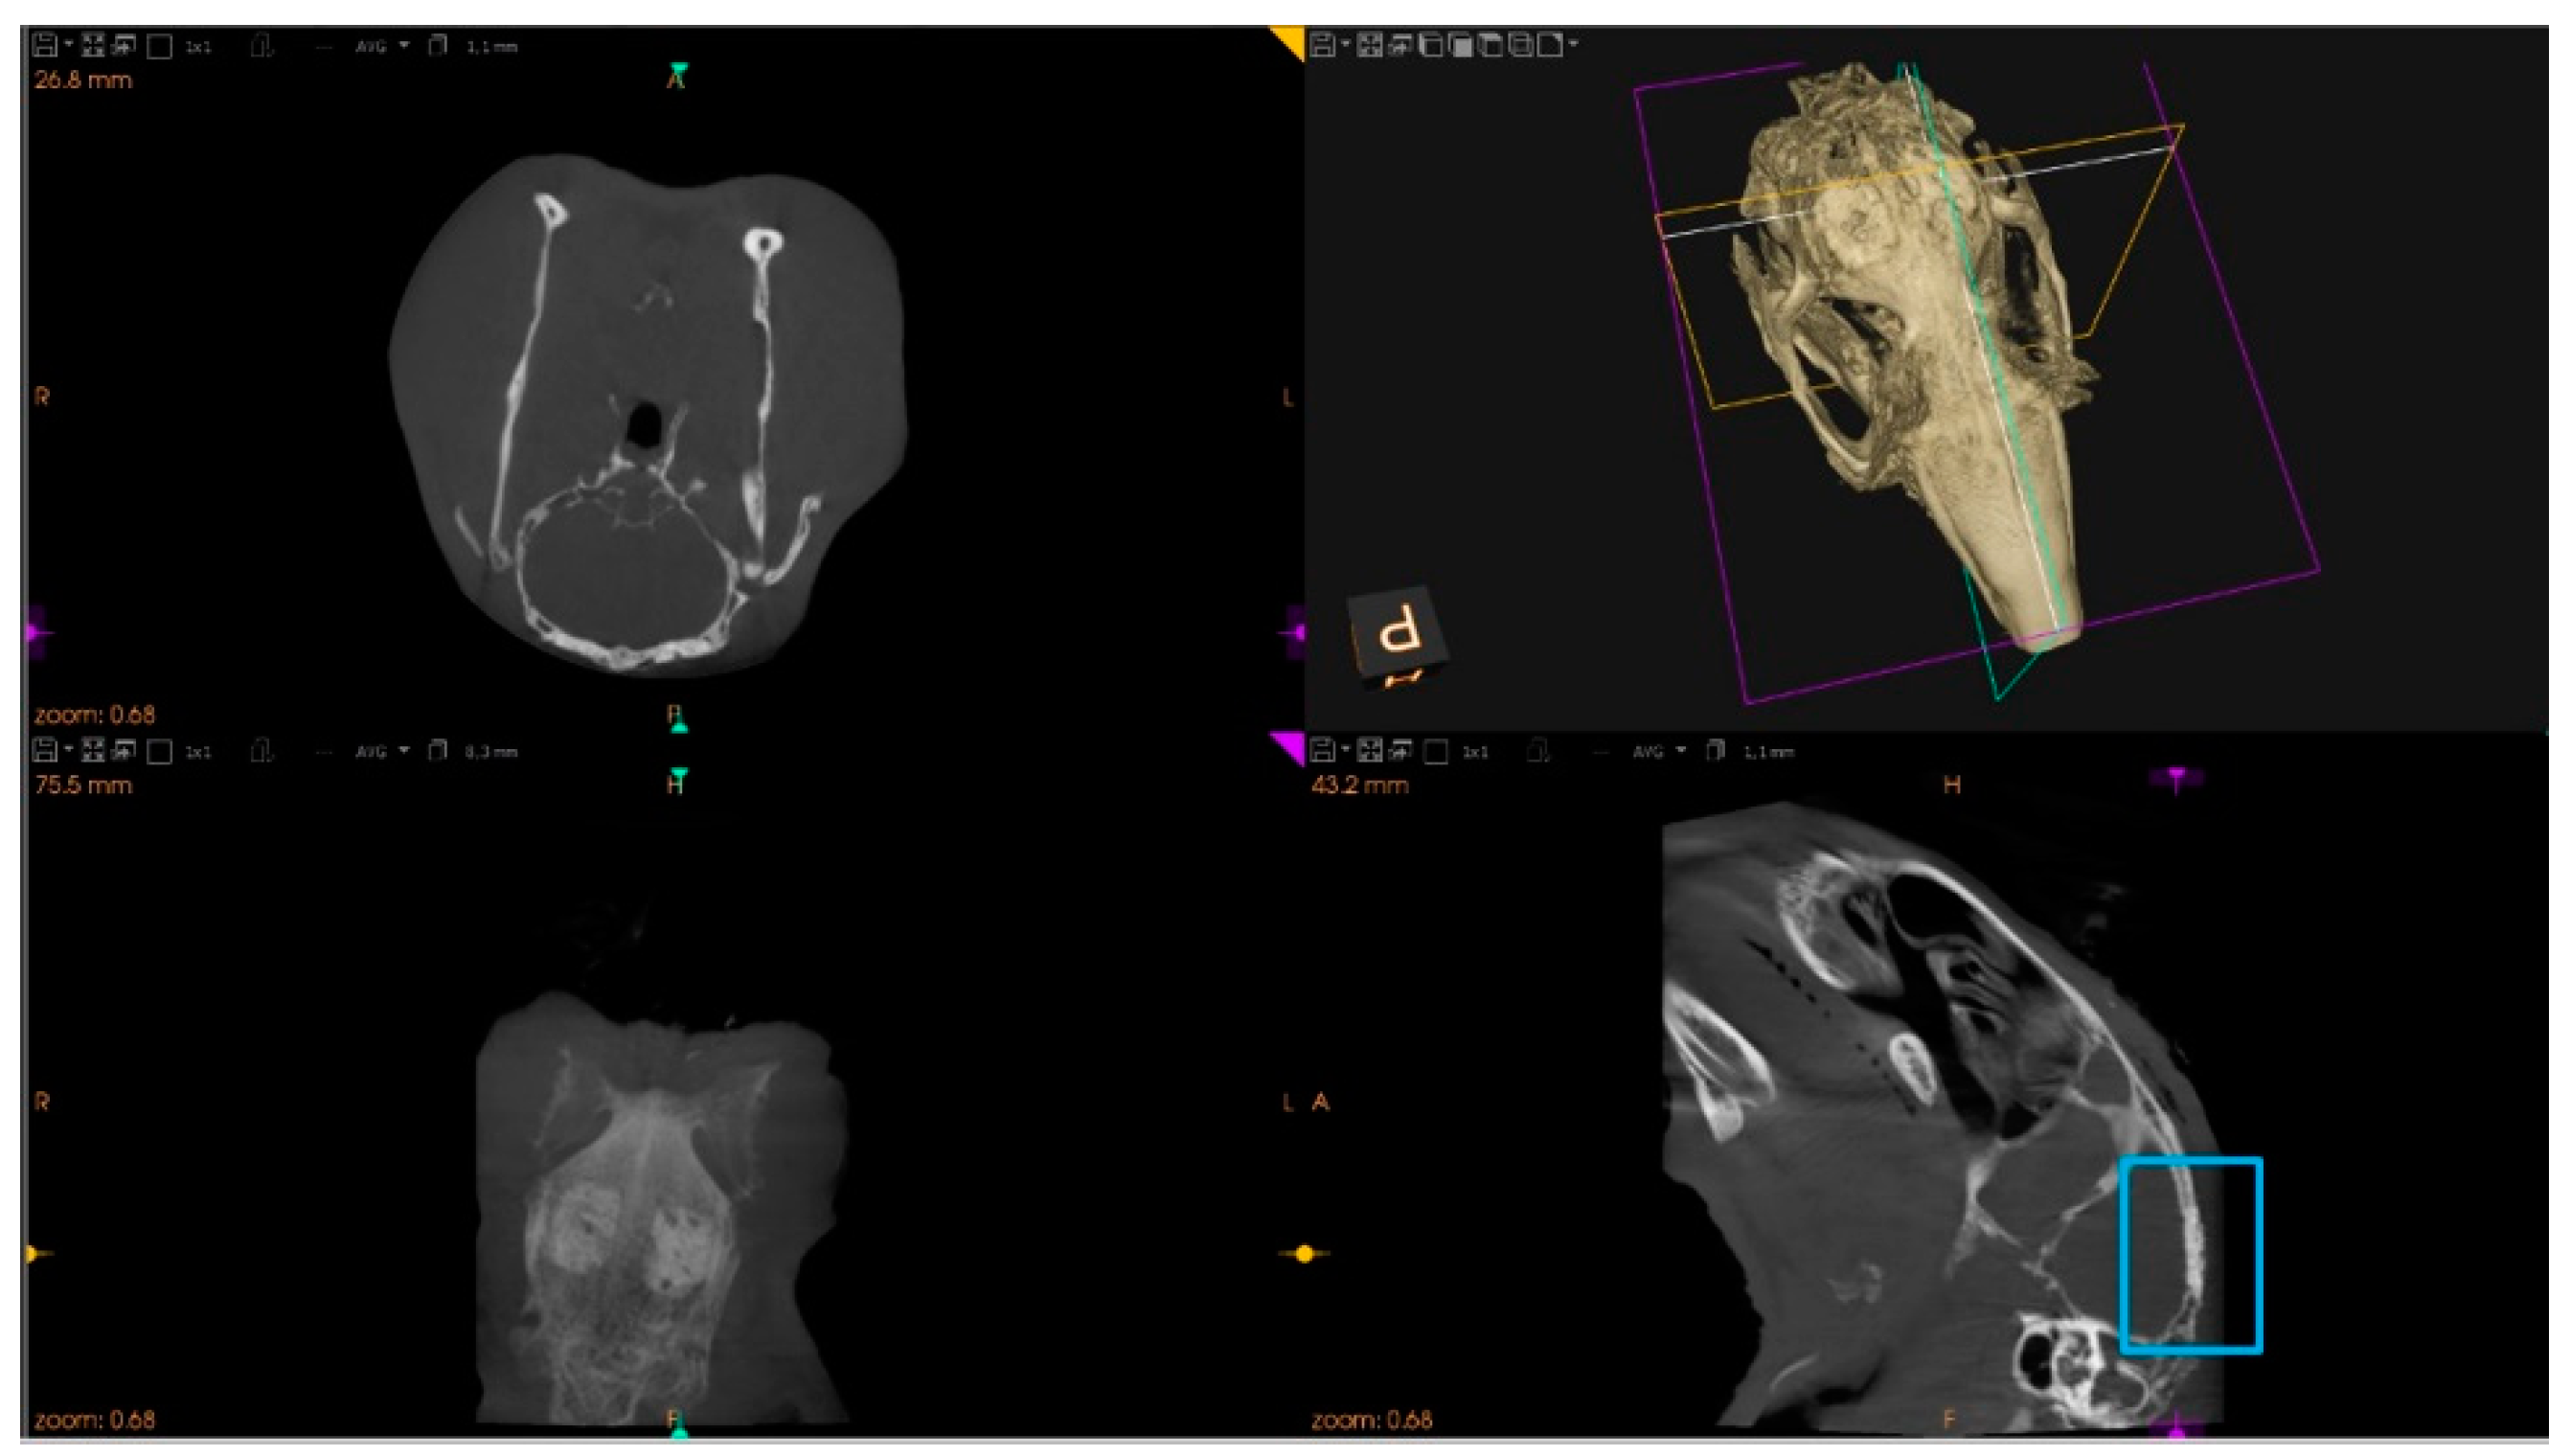

2.7.1. Microtomographic Evaluation

3.2. The Bone Healing in Rabbit Calvarial Critical Size Defects

3.3. Secretome Modulation of the Bone Healing Process